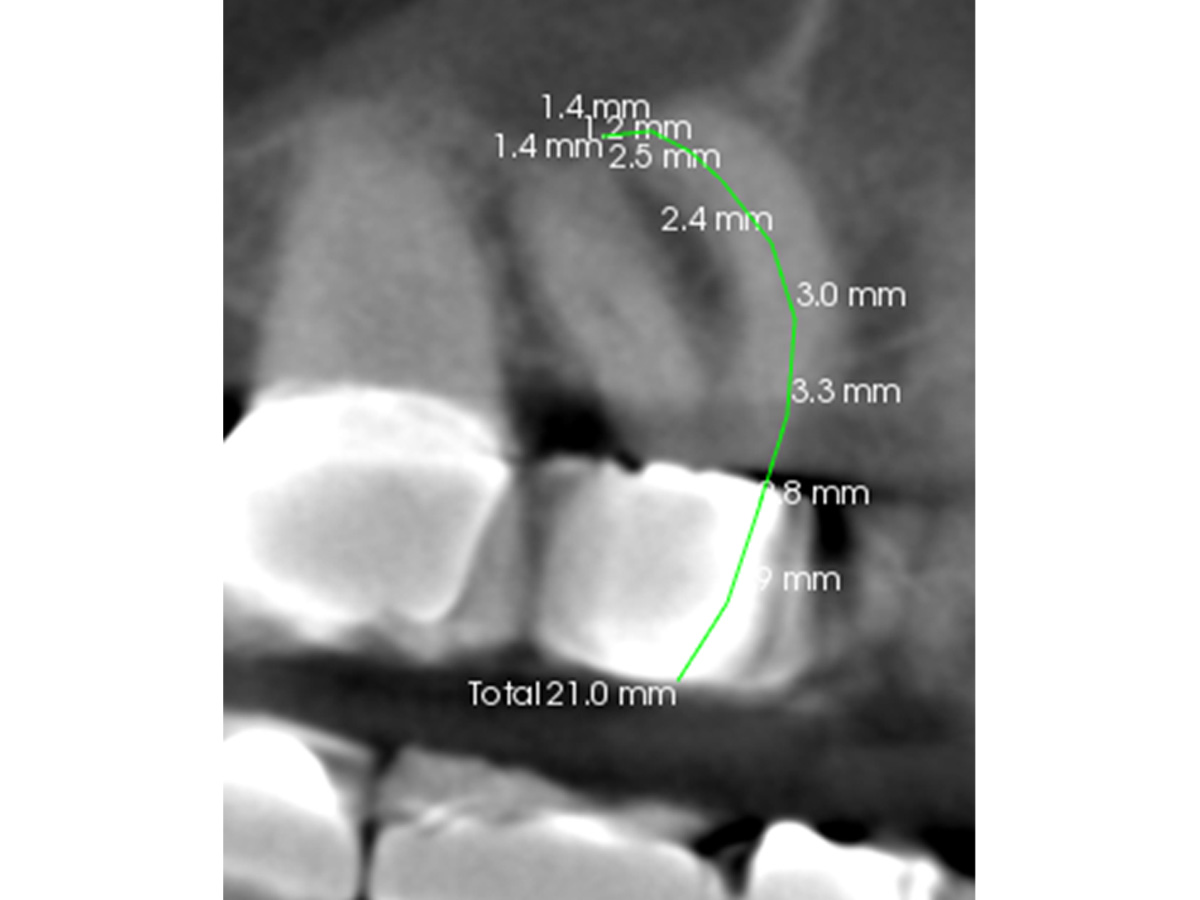

Abbildung 2

Nach der DVT-Untersuchung (Kodak 9000 3D, Auflösung 0,076 mm) bestätigte sich eine apikale Parodontitis an Zahn 16 palatinal. Eine Wurzelkanalbehandlung an Zahn 16 ist indiziert.